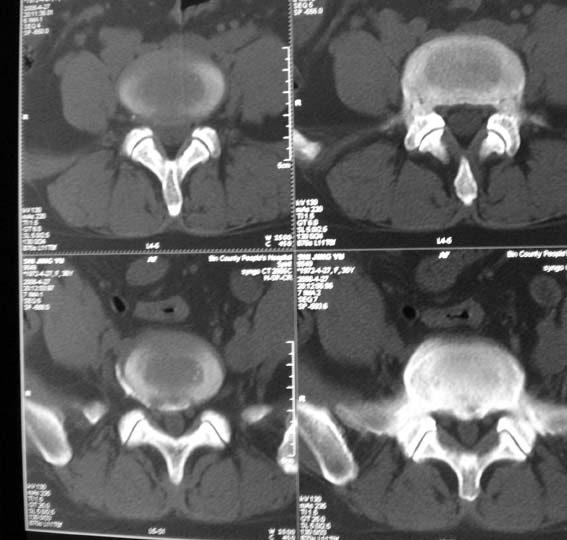

女,36岁,腰痛多年,坐久后,起身疼痛难忍。

腰4/5椎间盘轻度膨出,腰5/骶1椎间盘突出(右旁中央型)伴局部椎间盘钙化。

后纵韧带钙化。

腰4/5椎间盘轻度膨出,腰5/骶1椎间盘突出(右旁中央型)伴局部椎间盘钙化、右侧n根受压。